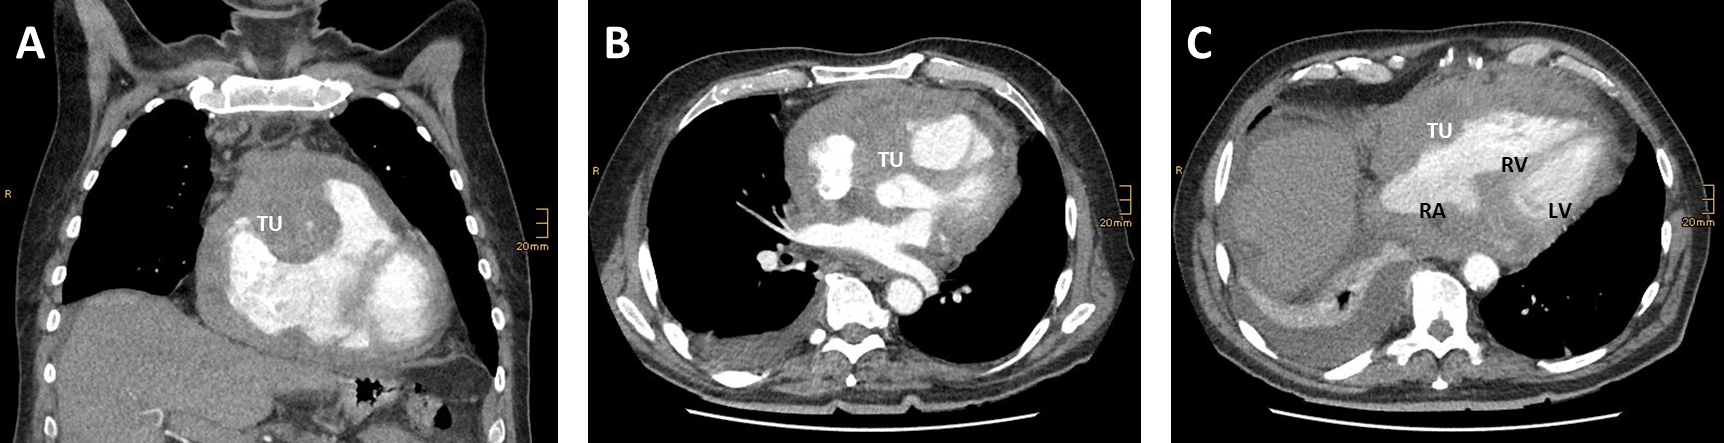

It has been shown decades ago that transthoracic echo (TTE) is sensitive and

specific for cardiac tamponade and can be used to measure the effusion volume

[37, 38]. Flow over the mitral- and trikuspidal-valve are dependent on in- and

expiration and differences are increased in pericardial effusion [39]. Today,

hemodynamic relevant tamponades are characterized by complete collapse of the

right atrium (

Fig. 2.Ultrasound in obstructive shock. (A) TTE shows a wormously configured thrombus in the right atrium with clearly dilated right ventricles and completely emptied left ventricle. RA, right atrium; RV, right ventricle; LA, left atrium. (B) Lung sonography (LUS) shows A-lines and a missing lung sliding (white arrow), while lung on the right side is normal. (C) TTE shows a large pericardial effusion (white arrows) with swinging heart. RA, right atrium; RV, right ventricle; LA, left atrium; LV, left ventricle.